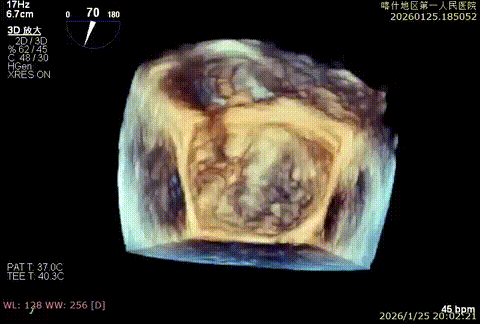

手术策略与手术过程

该例患者为DMR,脱垂区域较宽,术前制定手术策略:使用2把XTR先于患者外侧交界至1区部位进行钳夹。术中房间隔穿刺高度为4.0cm。成功穿刺后将SGC和XTR-CDS依次送入左心房,通过操控“M”旋钮调节SGC,使二尖瓣夹避开华法林脊,成功定位于2区正上方。在2区进行弹道测试成功后,进行Orientation调整。第一把于外侧交界区夹持,第二把于1区夹持,术中成功捕捞和夹持瓣叶后缓慢关紧夹臂,TEE检查见二尖瓣反流程度降低至1+,术后平均跨瓣压差3mmHg,手术顺利结束。

重度反流

SCG进入左房

3D enface进行Orientation调整